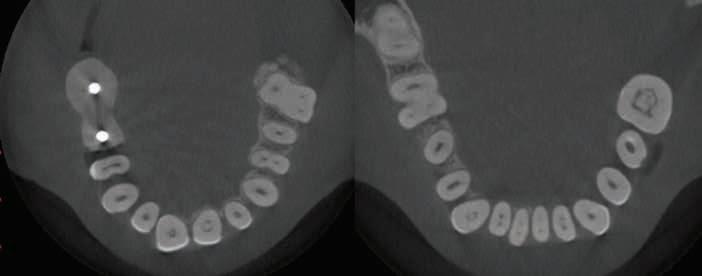

showing distinct pulp stones in canals of teeth #8, 9, 19, 23, 24,

4B. 8X8 CM MORITA ACCUITOMO 170 CONE BEAM CT SCAN—Sagittal and coronal view showing distinct pulp stones in canals of teeth #6, 7, 8, 9, 10, 11, 14. Multiple stones are noticed in the pulp chamber of 14.

Figure 4A. 8X8 CM MORITA ACCUITOMO 170 CONE BEAM CT SCAN—Axial view

25, 26, 27.

Figure

Figure 4C. 8X8 CM MORITA ACCUITOMO 170 CONE BEAM CT SCAN—Sagittal and coronal view showing distinct multiple pulp stones in canals of teeth #19, 22, 23, 24, 25, 26, 30. Single stones noticed in #27, 28, 31.